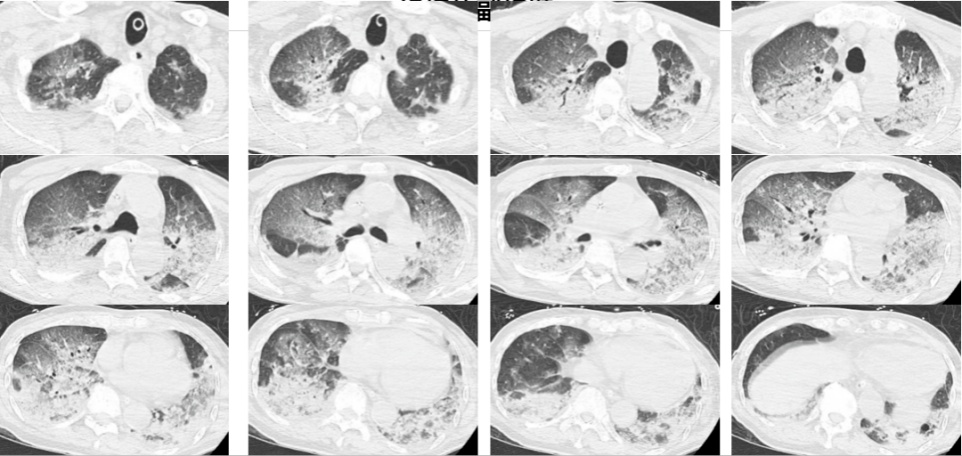

入院时,韩爷爷意识不清,血压、心率下降,医生随即为他安排头颅、胸部CT和肺血管CTA检查,结果显示,老人的双肺出现大面积白色影像。经会诊,韩爷爷被确诊为热射病诱发的肺水肿。

图源:潮新闻